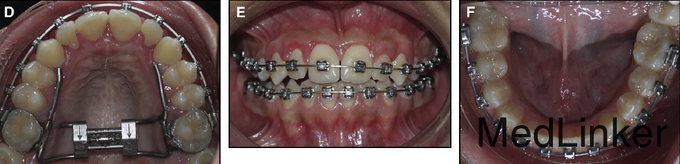

诊断:上牙弓严重横向不调。治疗:上颌颊侧骨皮质切开术+固定矫治+上颌腭侧固定扩弓。上颌上拖槽一周后行骨皮质切开术,如图,切开后全层翻瓣暴露骨皮质,于骨皮质上打孔,范围从牙槽骨顶端下方2mm到根尖下方2mm。根据牙槽厚度孔的深度从0.5mm到1.5mm不等,复位后间断缝合。同时腭侧粘接由带环,螺旋扩弓器制作的固定扩弓装置,即刻加力,转动完整的一圈。之后每周扩弓器打开1mm,连续8周,上颌牙弓被打开,扩弓器再维持2月,同时固定矫治器继续排齐整平。总疗程5个月2周。上颌宽度变化第一前磨牙间增加10mm,第二前磨牙间增加8.9mm,第一磨牙间增加8.3mm。但尖牙间宽度不变,这也是为什么扩弓后后期牙弓能够保持的原因,尖牙间宽度对维持牙弓稳定性非常重要。